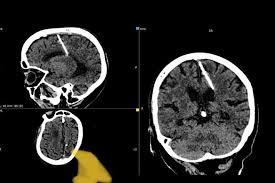

Cây kim được cho đã nằm trong não bệnh nhân 80 năm.

Cũng theo Sở Y tế Sakhalin, trong trường hợp này, cây kim dài gần 3cm đã đâm vào thùy đỉnh trái, nhưng không tạo ra tác dụng như mong muốn. Bà lão đã chung sống với cây kim mà không hề hay biết trong suốt 80 năm qua. Bà cũng chưa từng phàn nàn về việc bị đau đầu.

Mọi chuyện chỉ được phát hiện, khi bà lão đi khám và chụp CT. Các bác sĩ quyết định sẽ không rút cây kim vì lo sợ nó có thể gây ảnh hướng xấu tới bệnh nhân.